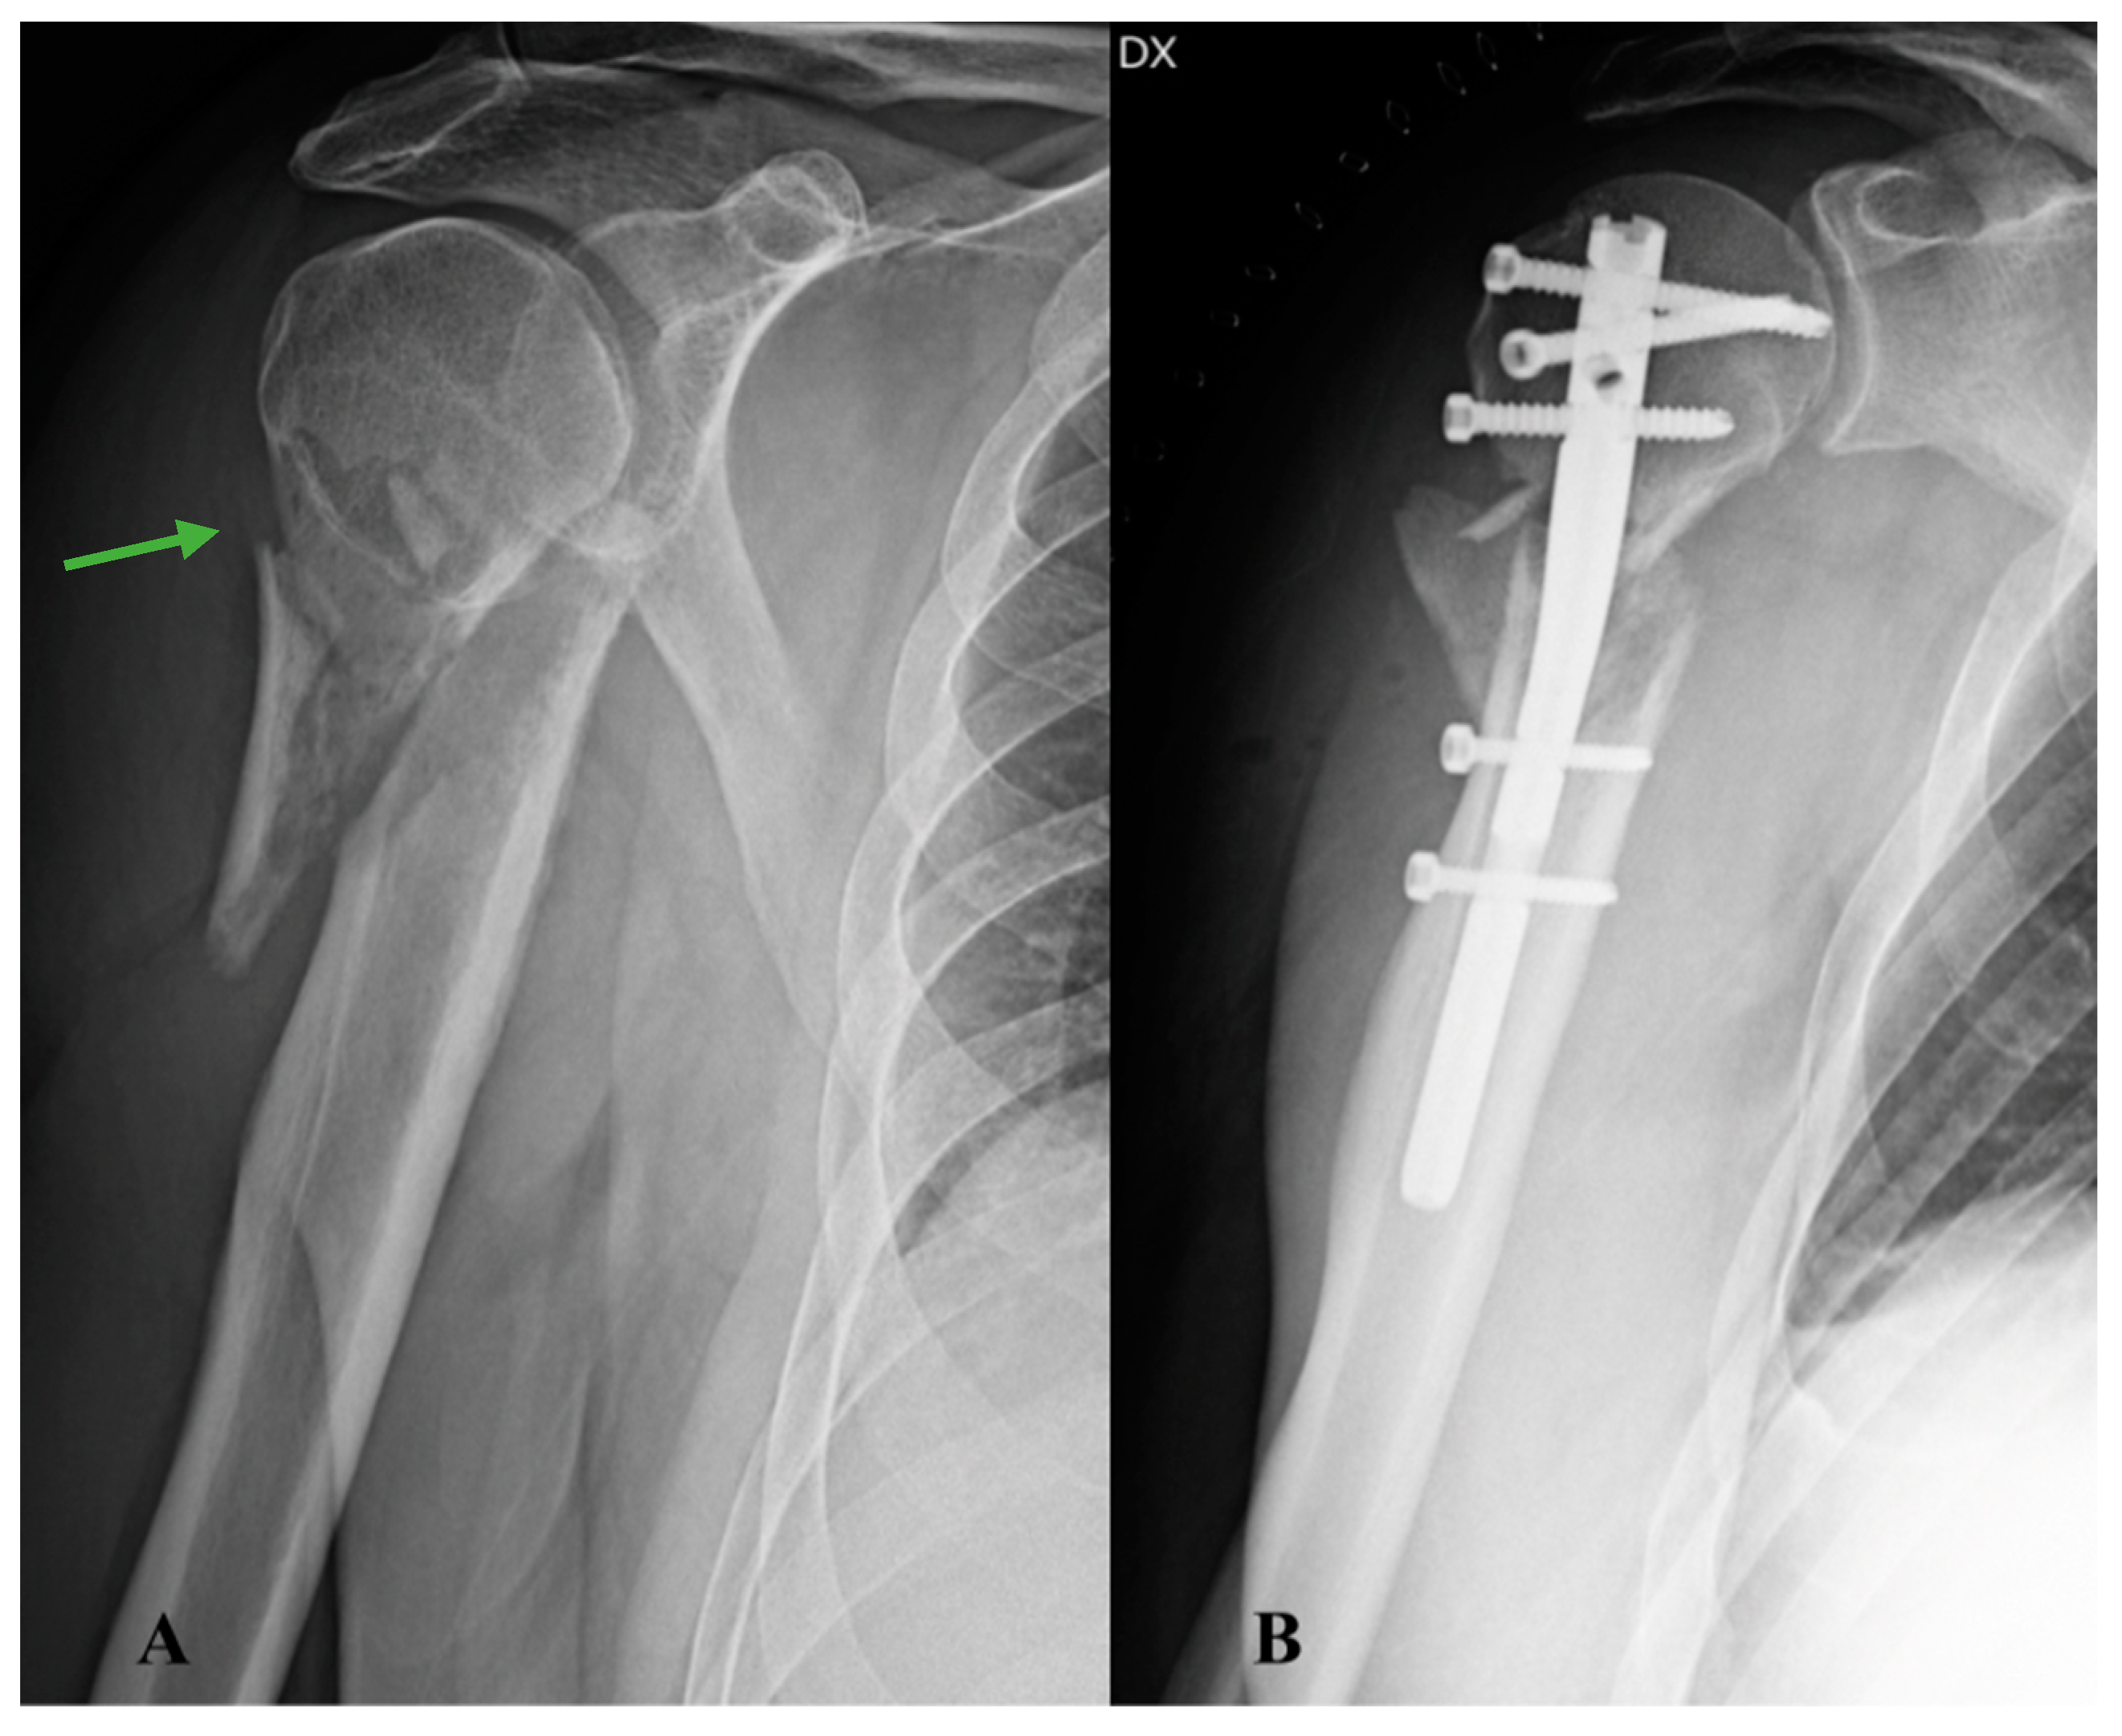

The evolution of the patient’s clinical picture upon returning home was partly monitored with telemedicine [7] through the installation of an application on a mobile device which allowed direct and continuous communication with healthcare professionals, thus allowing personalised treatment, intensification of follow-ups, and adequate continuity of care, while simplifying the patient’s care relationship. At the 1-month FU, the patient reported subjective well-being, good control of blood pressure, and absence of secondary displacements on radiographic control. For this reason, an adequate rehabilitation program was planned aimed at recovering joint function and gradually restoring physiological limb proprioception. At the FU approximately two months after the operation, the patient complained of worsening pain in the operated limb and functional limitation of the shoulder. The operated area appeared swollen, oedematous, and red. The shoulder radiograph highlighted an extensive area of humeral metadiaphyseal osteolysis (Figure 2A), not present in the previous instrumental images. For this reason, it was decided to perform a CT examination of the shoulder, which confirmed the presence of an osteolytic lesion associated with the presence of pathological tissue at the level of the periskeletal system on the postero-medial humeral side (Figure 2B).

Figure 2. X-ray and CT scan at 2-month FU: (A) antero-posterior radiograph of the shoulder showing an area of extensive humeral metadiaphyseal osteolysis (red arrow); (B) CT image of the shoulder in coronal section documenting the presence of pathological tissue at the periskeletal level in the postero-medial aspect of the arm (green arrow).